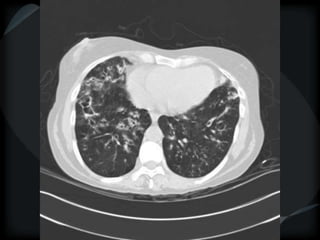

Septal Pattern – lymphatic/venous

 Secondary lobule outlined- interlobular septum

● Smooth – pulmonary veno-occlusive disease, mitral

stenosis, capillary hemangiomatosis, LC

● Beaded – lymphangitic carcinomatosis, lymphoma,

lymphangiomatosis, sarcoid

Rare = non-Langerhans’ cell histiocytosis (bone+pleura)

amyloidosis

smooth

LC

beaded

PHTN – PA 39mm

39.2mm

PHTN and septal thickening

? PVOD